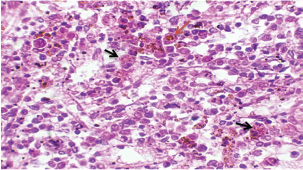

Histopathological examination of rabbits infected with T. annulata (G2) demonstrated progressive pathological alterations in various organs, in contrast to the control group (G1), which exhibited no abnormalities. At 14 days of post-infection, the lungs exhibited moderate alveolar thickening, hyperemia, and the presence of developed schizonts, indicating early tissue involvement (Fig. 4). The liver showed multiple necrotic areas, extensive venous congestion, and parasitized red blood cells, suggesting severe hepatic distress (Fig. 5). The spleen exhibited scattered macrophages containing microschizonts and hemosiderin-laden macrophages, reflecting both immune activation and erythrocyte breakdown (Fig. 6). The kidneys were affected by tubular infiltration with parasitized mononuclear cells (MNCs) (Fig. 7), whereas the mesenteric lymph nodes showed marked architectural disruption and merozoite aggregation (Fig. 8), suggesting significant immune system involvement.

Fig. 5. A histopathological section of the liver of (G2) at 14 days postinfection exhibits multiple necrotic findings in the liver parenchyma with extensive venous congestion and dilatation associated with numbers of parasitized red blood cells (black arrow) (H&E stain X 40).

Fig. 7. A histopathological section of kidney of (G2) at 14 days postinfection showing tubular infiltration with parasitized mononuclear cells (black arrow) (H&E stain X 40).